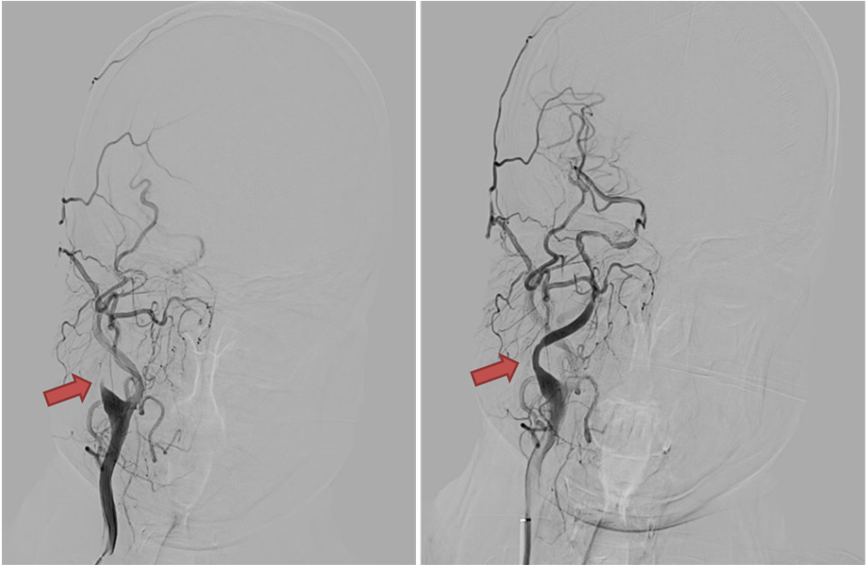

手术由介入小组及李红霞护士长带领的介入手术室共同完成。术中在影像引导下,主刀医师精细操作导丝与微导管穿越闭塞段,在保护伞的保护下,吸出了大量陈旧的血栓,逐步完成血管开通,最终成功开通闭塞血管并恢复有效灌注,术中无血栓逃逸。术后一个多月随访显示,患者未再出现卒中症状发作,之前存在的视物模糊也明显好转,生活质量得到保障。

术前、术后正位比较